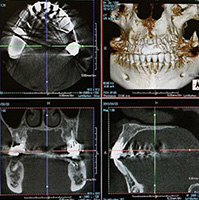

特徴2:CT(三次元立体画像撮影装置)による精密分析

歯周病治療を行う際は、歯や歯ぐきの表面的な状態だけでなく、歯槽骨の状態を正確に把握することが重要です。当院では、三次元立体画像撮影装置(CT)を用いてお口の中を多角的に解析し、歯槽骨の吸収具合や歯の根の形態などを詳細に確認しています。

従来のレントゲンだけでは把握しきれない部位まで精密にチェックすることで、治療計画をより適切に立案することが可能となります。特に、外科的処置が必要な中等度から重度の歯周病においては、骨の高さや厚み、歯根の走行などが治療方針を決める上で大きな要因となります。

CT画像を活用することで、患者さんにもご自身のお口の中の状況を立体的にイメージしていただきやすくなり、治療方針の説明を理解しやすくなります。精密分析を行うことにより、無駄な治療を避け、より安全かつ効果的なアプローチが可能です。